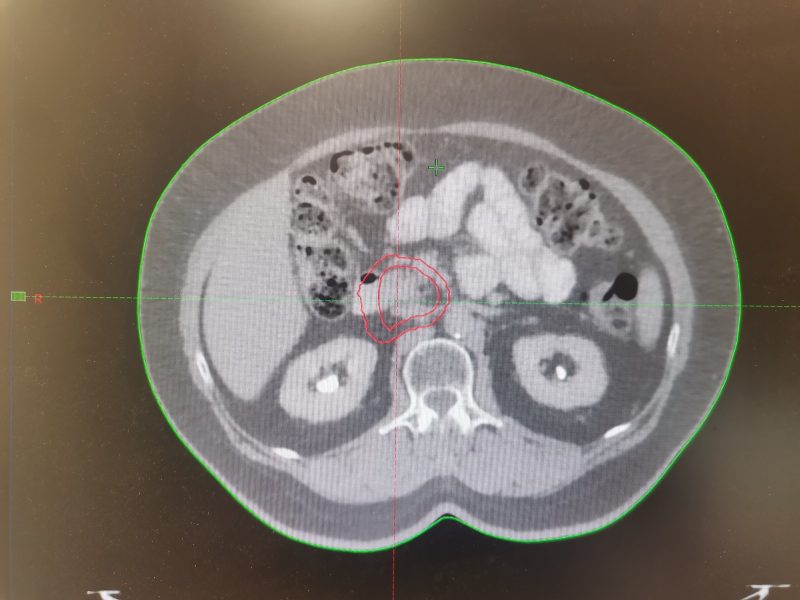

Клинический пример: Пациентка 67 лет с неоперабельным раком головки поджелудочной железы.

В начале 2023г обратилась в больницу с жалобами на боли в эпигастрии, желтушность кожных покровов и склер глаз. При обследовании выявлена опухоль размерами 32х22 мм, которая сдавила желчные протоки, нарушила отток желчи и привела к развитию желтухи. Опухоль признана неоперабельной. Пациентке хирургическим путем установлен стент. Назначены курсы лекарственной терапии, которые привели к стабилизации процесса. На консилиуме было принято решение провести стереотаксическую лучевую терапию для уменьшения размеров опухоли. После КТ-топометрии на задержке дыхания выполнено оконтуривание и физико-дозиметрический расчет. Проведено 5 сеансов СТЛТ под ежедневным контролем укладки лечащим врачом-радиотерапевтом и медицинским физиком. Контроль мишени осуществлялся совмещением снимков пациентки в реальном времени со сканами КТ-топометрии. В процессе лечения и после его окончания побочных эффектов не отмечено. На контрольном МРТ через 3 месяца- выраженный лечебный эффект (опухоль не визуализируется). В настоящий момент женщина находится в процессе лекарственной терапии.

Январь 2023 года. Март 2026 года